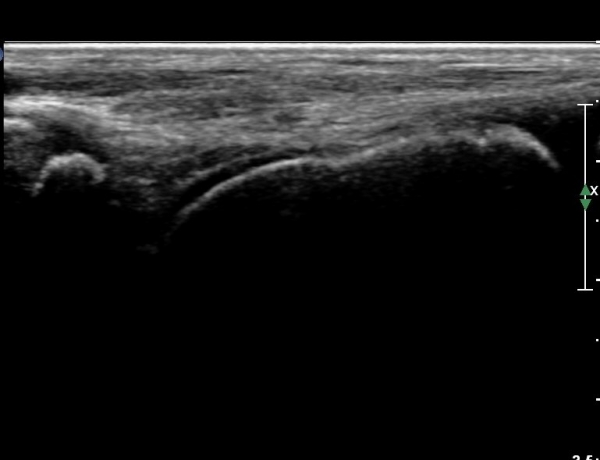

ÃÊÀ½ÆÄ °Ë»ç